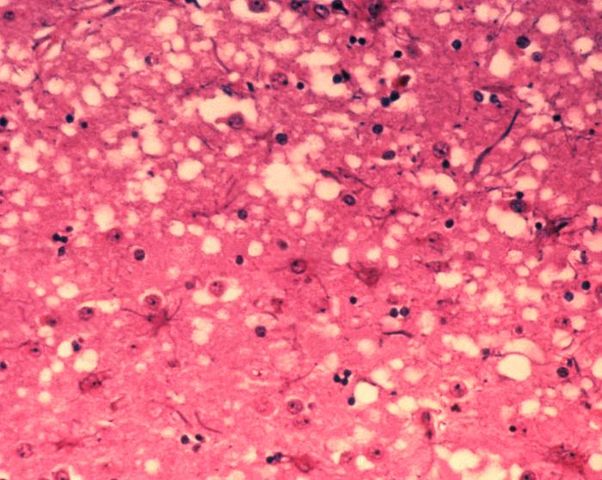

English: This micrograph of brain tissue reveals the cytoarchitectural histopathologic changes found in bovine spongiform encephalopathy. The presence of vacuoles, i.e. microscopic “holes” in the gray matter, gives the brain of BSE-affected cows a sponge-like appearance when tissue sections are examined in the lab.

Nederlands: Deze microscopische opname toont hersenweefsel van een koe die aan BSE gestorven is. Tussen de hersencellen ziet men duidelijk verschillende vacuoles, die deze coupe (weefselsnede) een sponsachtig uitzicht geven.

Deutsch: Das Bild zeigt die histopathologischen Veränderungen die bei einer Infektion mit BSE auftreten. Die Vakuolen, die in der grauen Substanz (substantia grisea) auftreten geben dem Bild ein schwamm-artiges Aussehen.

Français : Cette coupe de tissu cérébral montre les modifications histopathologiques de l'organisation cellulaire lors d'une encéphalopathie spongiforme bovine. la présence de vacuoles, c'est-à-dire des "trous" microscopiques dans le tissu cérébral, donne au cerveau de vaches atteintes de l'ESB un aspect en éponge à l'examen des tissus en laboratoire.